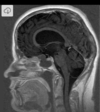

Qual é o padrão de Chiari I

Deslocamento caudal das tonsilas cerebelares > 6 mm (infância) Associação com Hidro-siringomielia 70%

Qual é o padrão de Chiari II (arnold-chiari)

Deslocamento caudal das tonsilas cerebelares, do tronco cerebral, da medula oblonga, do IV ventrículo; Associação com Mielomeningocele; Craniolacunia (lesão radioluscente na calota); Disgenesia do corpo caloso Inserção baixa da tenda do cerebelo e baixa da tórcula (contrário de dandy), Herniação superior do cerebelo (com aspecto em torre), comprimindo o mesencéfalo e causando o tectum em bico. Clivus encurtado, fossa posterior pequena (contrário de dandy), curso anatomico alterado das artérias cerebelares postero inferiores (PAICAS); Anormalidades supratentoriais: Ventriculomegalia supratentorial, angulação anterior e inferior dos cornos frontais (aparência em asa de morcego), Colpocefalia (cornos occipitais maiores que os frontais dos ventrículos laterais), fenestração da foice cerebral (hipoplasica) com interdigitação dos giros corticais;